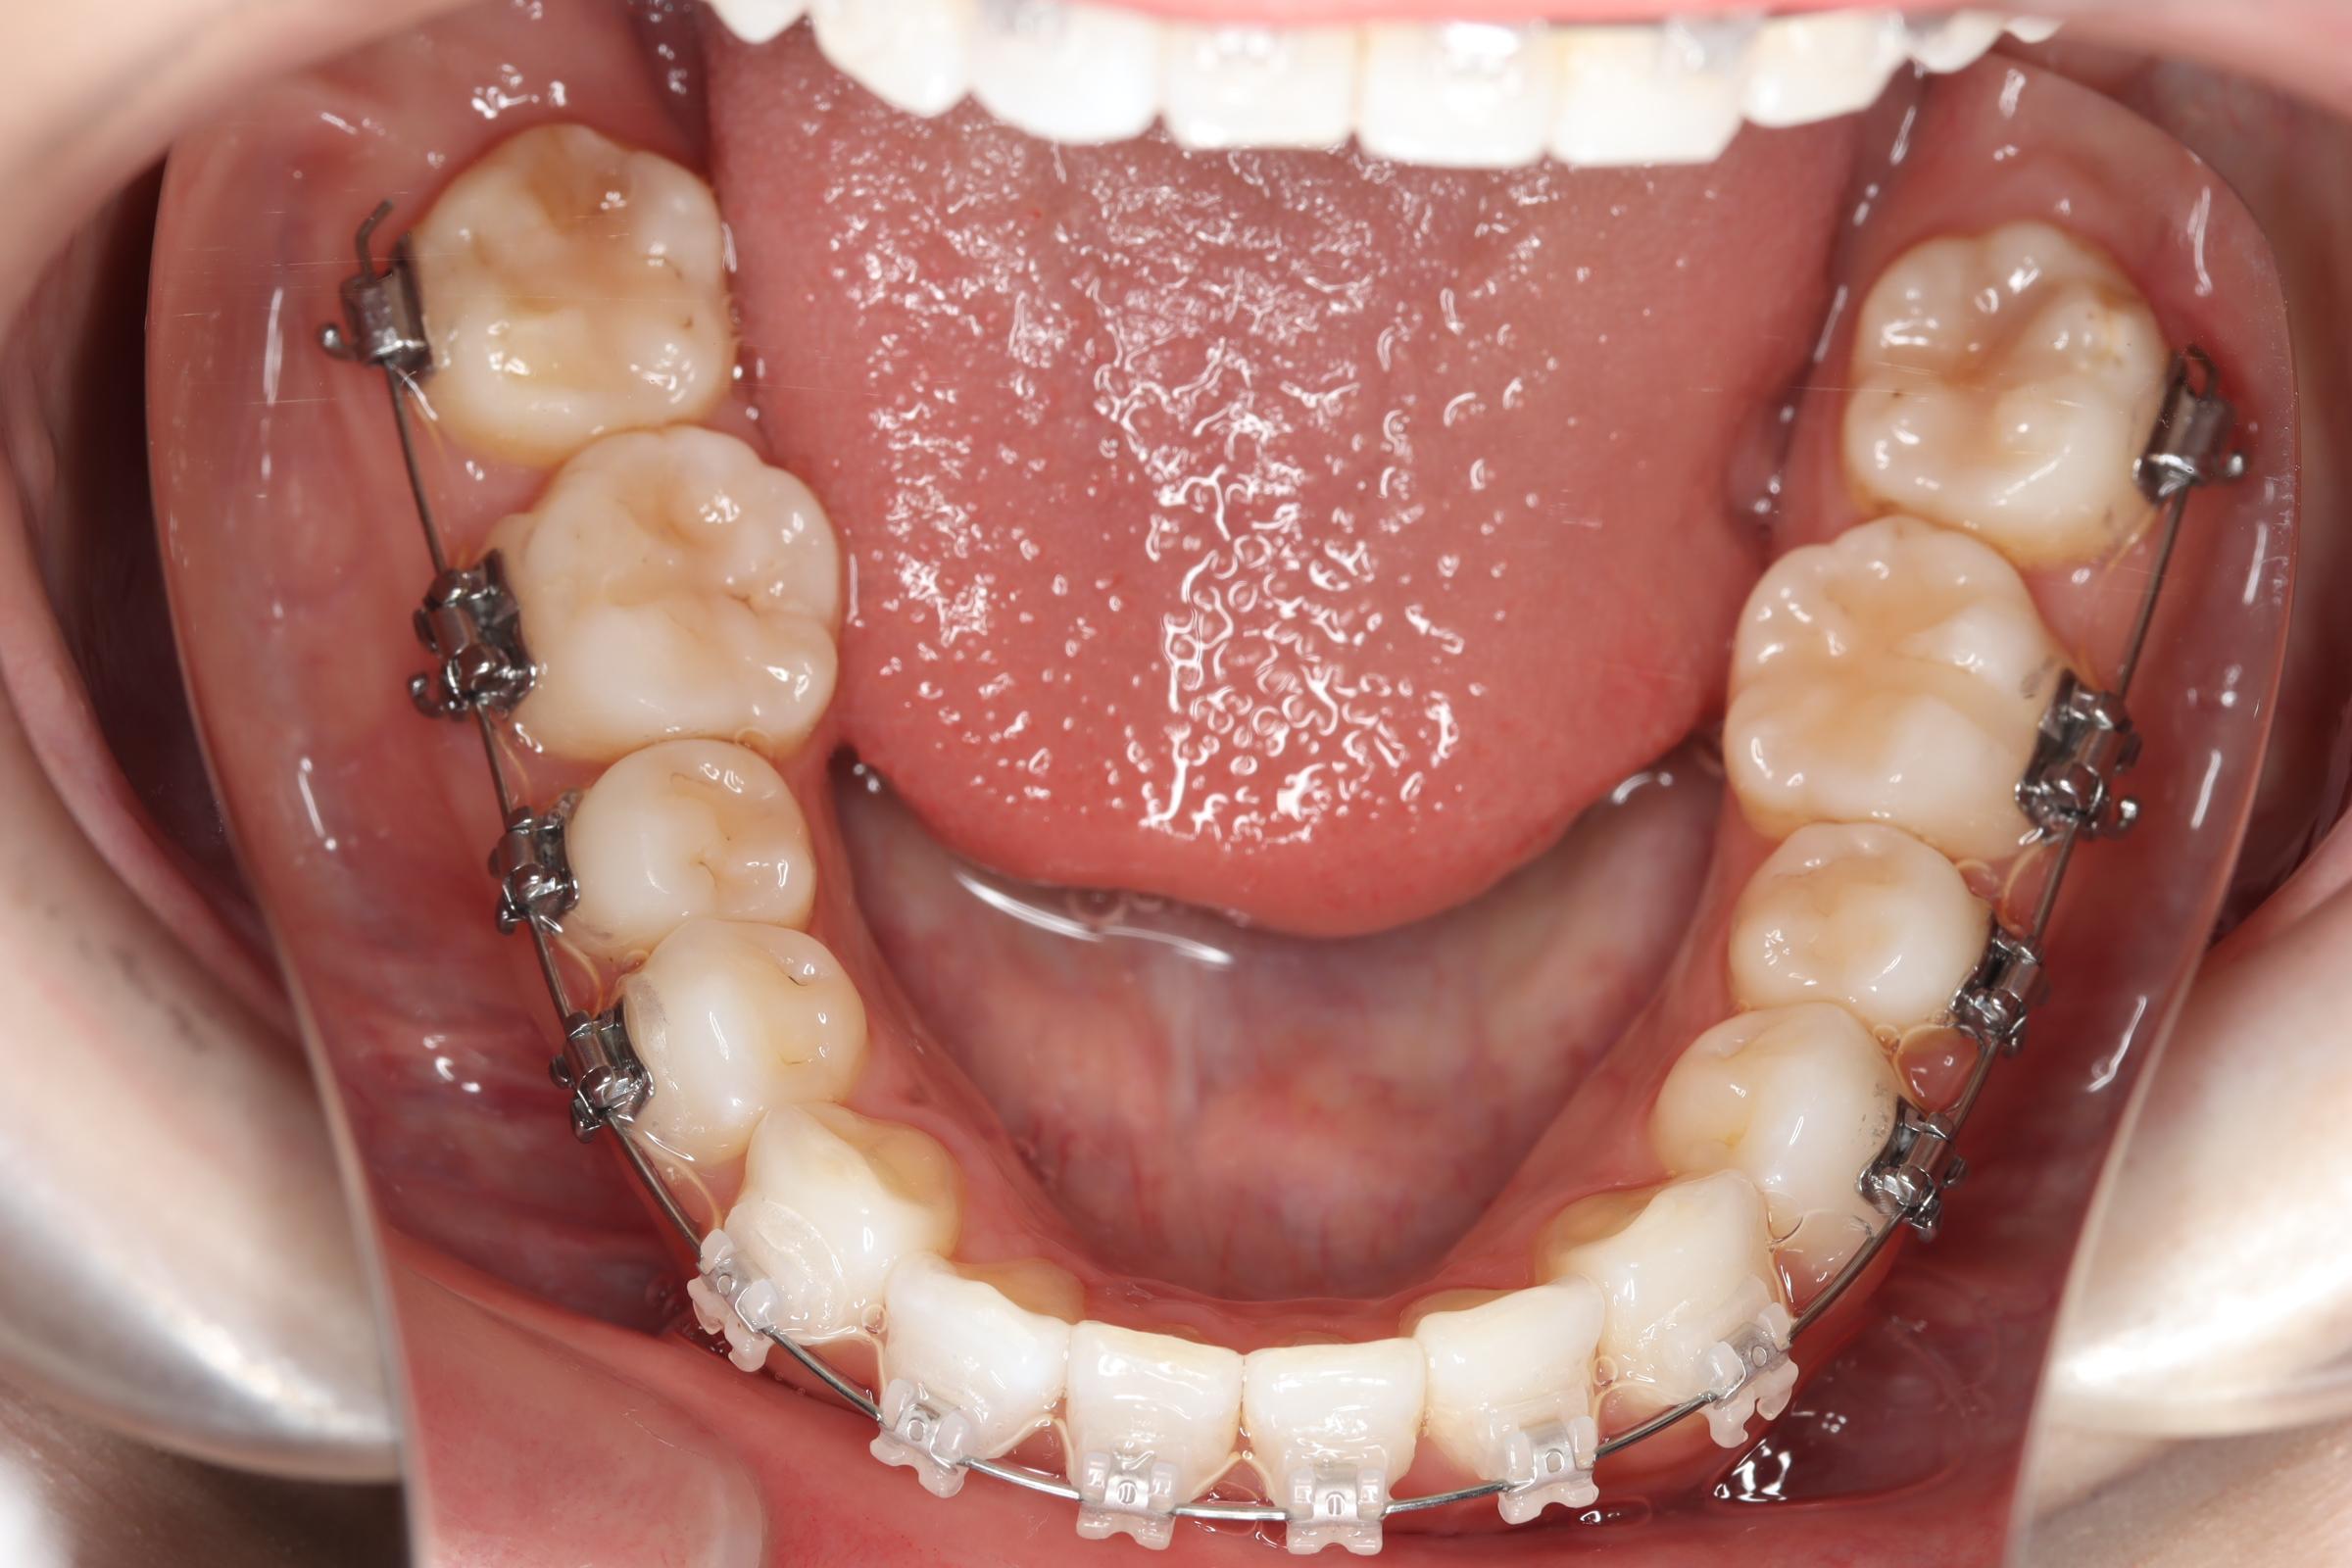

治療中

![]() | ![]() | ![]() |

| 使用矯正装置 | 上顎:セルフライゲーションリンガルブラケット 下顎:セルフライゲーションブラケット(セラミッククリッピー) 歯科矯正用アンカースクリュー |